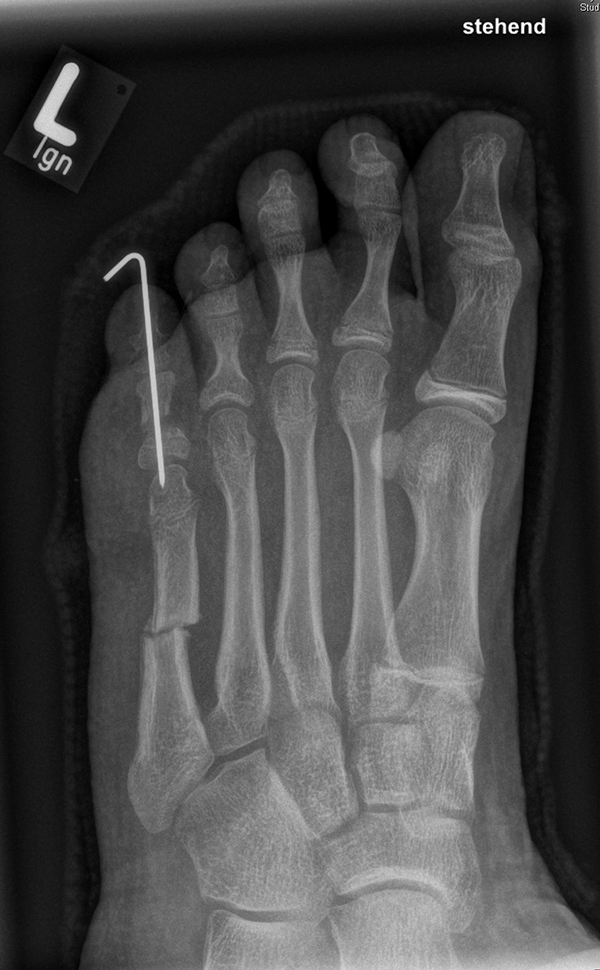

Calcaneus-Osteotomie

Die minimalinvasive Calcaneusverschiebeosteotomie bietet eindeutige Vorteile gegenüber dem offenen Verfahren, sodass wir bei Kindern und Jugendlichen nahezu keine offene Verschiebeosteotomie mehr durchführen. Am Calcaneus liegt die offene Wachstumsfuge dorsal. Bei der Durchführung müssen Schenkel der V-förmigen Osteotomie daher etwas steiler angelegt werden, in einem stumpfen Winkel (siehe Abb. 3 a-j). Für die Osteotomie liegen unsere Patienten auf dem Rücken und der BV wird für die exakte Seitaufnahme eingestellt. Der Fuß lagert auf einem hohen OP-Kissen und die Osteotomie kann bequem mit einem langen Kirschner-Draht und einem sterilen Stift angezeichnet werden (Abb. 15).

Damit lässt sich im Verlauf Röntgenstrahlung für die jungen Patienten vermeiden und die minimalinvasive Osteotomie kann sicher durchgeführt werden. Anschließend erfolgt die Verschiebung oder Impaktion. Ist ein Gleiten nach plantar oder cranial des distalen Fragmentes erwünscht, wird die Osteotomie schräg ohne V-Form entweder verlängernd oder verkürzend durchgeführt (Abb. 16).

Durch den knöchernen Defekt der Fräse gelingt die Verschiebung bei der minimalinvasiven Osteotomie im Fall von strukturell festen Klumpfüßen mit starkem Zug der verkürzten Achillessehne oder bei einer fixierenden spastischen Grunderkrankung einfacher gegenüber dem offen Verfahren. Ein weiteres Plus bei hyperaktiven Weichteilen ist die Vermeidung der ungewollten Cranialisierung des dorsalen Fragmentes durch die V-förmige Osteotomie (Abb. 16).

Die minimalinvasive Calcaneusverschiebeosoteotomie kommt somit in der Versorgung von kindlichen und jugendlichen Fußdeformitäten in einem weiten Erkrankungsspektrum zum Einsatz (Abb. 16):

- Plattfuß – Varisation

- Klumpfuß residual – Valgisation und ggfs. Cranialisation sowie Impaktion

- Klumpfuß überkorrigiert – Varisation und ggfs. Plantarisierung

- Hohlfuß – Cranialisation und ggf. Valgisation (alternativ minimalinvasive Austin-Osteotomie)

Abb. 16 a-f: Varisation einer valgischen Calcaneusstellung bei Knick-Senk-Fuß mit V-förmiger Osteotomie axiale Ansicht (a), seitliche Ansicht (b), d. p. Ansicht (c) und nach Entfernung der Drähte seitliche Ansicht (d), Caudalisierung des dorsalen Calcaneus bei iatrogenem Plattfuß nach Klumpfußüberkorrektur (e) und Cranialisierung beim Hohlfuß (f).

Zum Lesen der Bildbeschreibung und zur Vollansicht bitte die Bilder anklicken. Bilder: A. Helmers.